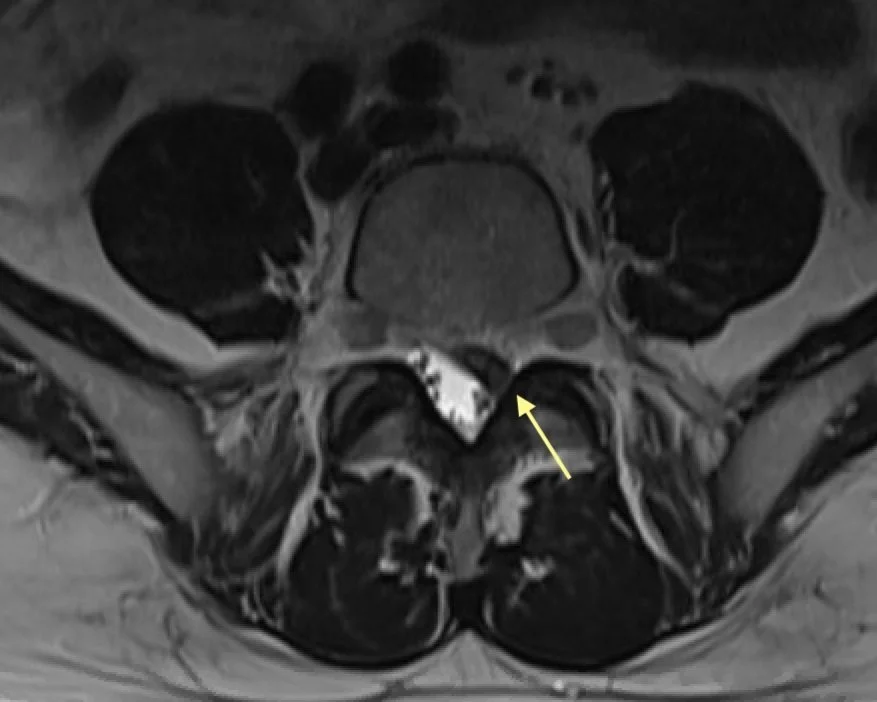

MRI Sagittal showing disc herniation causing radiculopathy

This MRI scan shows a large disc herniation (arrow) that is compressing the nerve (seen in gray). This patient ultimately underwent arthroplasty.